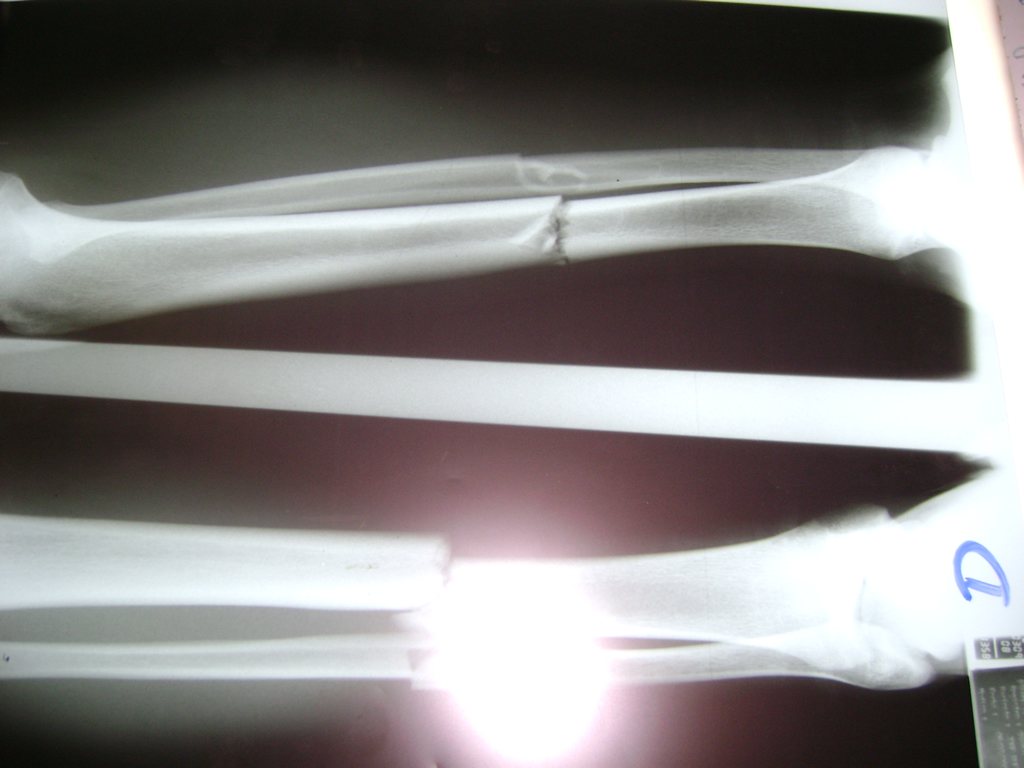

Cirugías de Codo - Perone y Tibia

Aunque cada uno de estos huesos puede fracturarse por separado, normalmente la rotura es una lesión que se produce de forma conjunta

La mayor parte de las roturas implican a la parte proximal del hueso (parte del hueso próximo a la rodilla) o a la parte distal (parte del hueso cerca del tobillo).

Debido a la fina cobertura de piel que recubre la tibia y el peroné, las fracturas generalmente son abiertas, es decir, el hueso roto rasga la piel, atravesándola. Las fracturas de tibia y peroné generalmente se producen por un fuerte impacto o torsión.